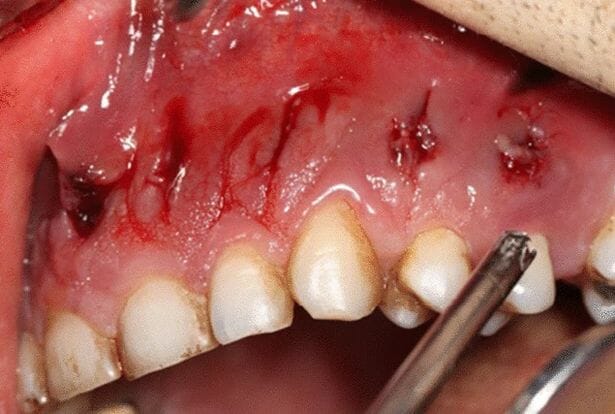

ووفقًا لتقرير نُشر في مجلة Journal of Medical Case Reports، في 3 مارس، تمت إحالة الرجل إلى خبير في التهابات اللثة اكتشف أنه مصاب بعدوى فطرية تأكل اللحم، تُعرف باسم فطار الغشاء المخاطي، تنمو في جزء من فكه السفلي.

وبعد التشخيص المرعب، اكتشف مسعفون من جامعة العلوم الطبية في طهران في وقت لاحق، أن الفطر قد انتشر في أجزاء من تجويفه الأنفي والفم.

وأمضى جراحو التجميل ساعات في إزالة 12 سنًا وعظام الوجه المصابة، لمنع المرض من الانتشار أكثر والتسبب في المزيد من المضاعفات.